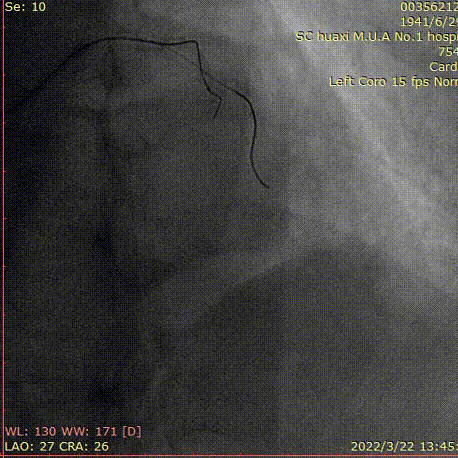

造影说明:右冠近段中度狭窄,向前降支无明显侧枝。